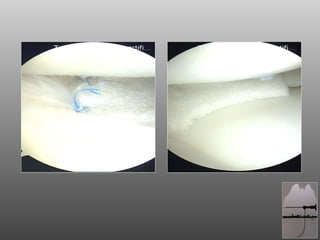

RAGAZZO DI 18aa, ATTIVO (CALCIO DILETTANTI) A 16aa SUTURA MENISCALE CORPO MENISCO ESTERNO OUT-IN  A 17 BLOCCO ARTICOLARE POST-TRAUMA: ARTROSCOPIA

RAGAZZO DI 18aa,ATTIVO (CALCIO DILETTANTI) A 16aa SUTURA MENISCALE CORPO MENISCO ESTERNO OUT-IN A 17 BLOCCO ARTICOLARE POST-TRAUMA: ARTROSCOPIA

SCAFFOLD MENISCALE Impiantabile per via artroscopica  Biocompatibile  Bioriassorbibile  Forma fisica simile a quella del menisco umano  Adattabile alle dimensioni del difetto ACTI fit

SCAFFOLD MENISCALE Impiantabileper via artroscopica Biocompatibile Bioriassorbibile Forma fisica simile a quella del menisco umano Adattabile alle dimensioni del difetto ACTI fit